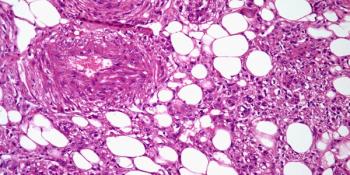

A 36-year-old man presents with a painless right arm mass. What is your diagnosis?